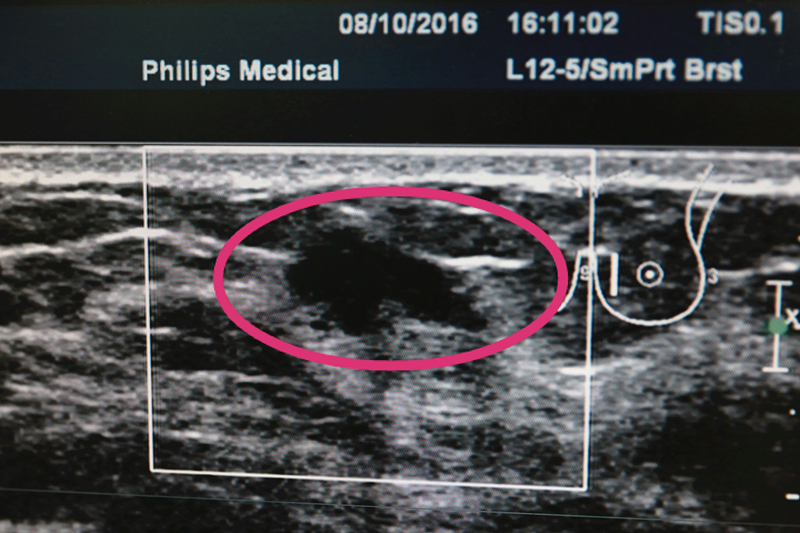

(超声检查下可见不规则结节)

“19岁,是我们乳腺外科接诊的最年轻的乳腺癌患者,以前,二三十岁的女性患上乳腺癌的情况比较少见,但近年来却出现了年轻化的趋势,去年,到我们乳腺外科就诊的20多岁的乳腺癌患者就有十几位。”烟台山医院乳腺外科副主任巩立国表示,好在小王的病情发现的比较早,治疗的比较科学、及时,才避免了更大的风险,“前段时间,她在进行健康体检的时候,在超声检查时发现左侧乳房有一个0.9厘米乘以0.7厘米的不规则的结节。此后,又到我们医院进行复查,根据我们的临床经验,初步判断她可能患上了乳腺癌,因此,我们建议病人进行手术,并进行病理检查以便确诊。”